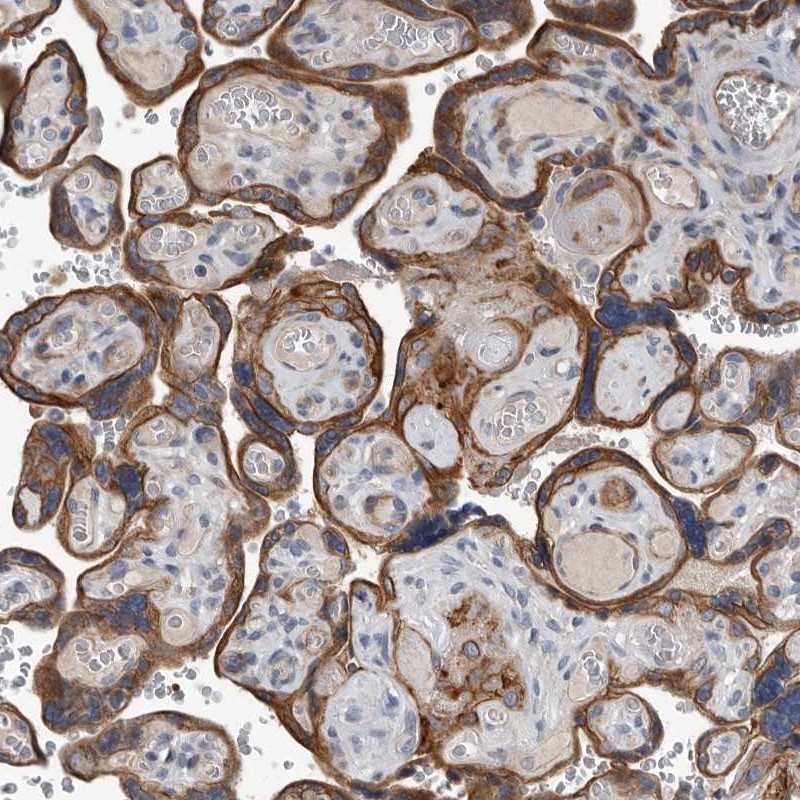

Immunohistochemical staining of human placenta shows distinct cytoplasmic and membranous positivity in trophoblasts.